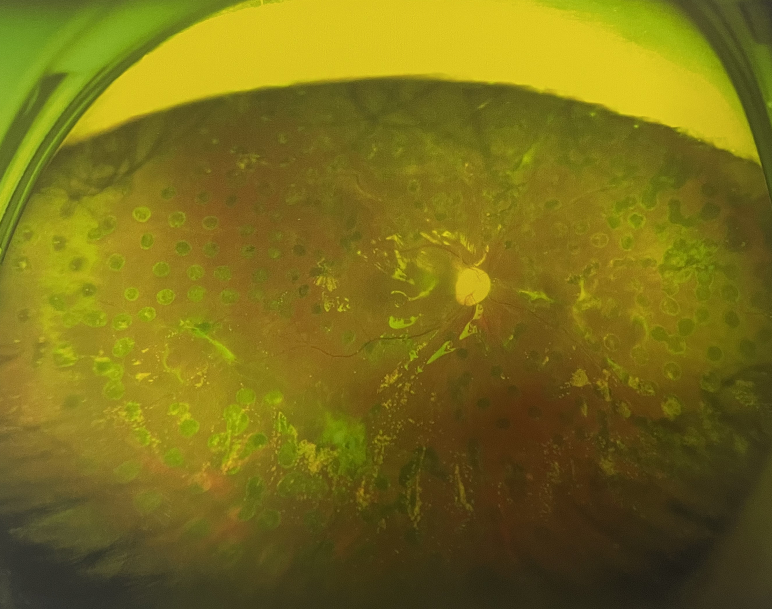

右眼術(shù)前

眼底病??茝埿』⑨t(yī)生檢查后,診斷王女士為“雙眼玻璃體積血、雙眼糖尿病視網(wǎng)膜病變V期”。(V期即5期,纖維增生期,出現(xiàn)纖維膜,可伴視網(wǎng)膜前出血或玻璃體出血。)

張小虎醫(yī)生為王女士進(jìn)行右眼玻璃體腔注藥術(shù),3天后進(jìn)行右眼23G玻璃體切割術(shù)后視力有所提升。

4個月后王女士來院取硅油,取油后視力恢復(fù)到0.6。“當(dāng)時來的時候真的只能看到模糊的影子,特別害怕覺得完了,想說眼睛估計要瞎了,沒想到手術(shù)后視力竟然提升了,現(xiàn)在也看得比較清楚了。”王女士說到。

張小虎醫(yī)生表示,糖網(wǎng)病進(jìn)展到嚴(yán)重增殖期帶來的視力損傷往往是極其嚴(yán)重的,目前王女士右眼從術(shù)前0.02恢復(fù)到術(shù)后0.6,已屬十分難得。